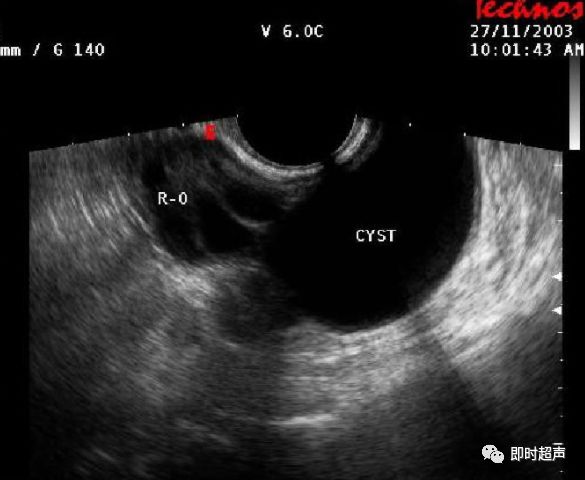

右侧卵巢ca声像图——zengerya - 超声医学讨论版 - 爱爱医医学论坛

图片尺寸762x534